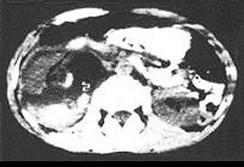

问题 男,建筑工人,不慎从3m高处跌下,臀部着地。当时无不适,约1小时后感左腰痛,排尿呈红色,尿显微镜检查见红细胞满视野,体检腹平软,无明显肿块。IVU无异常发现。应考虑诊断 ( )

选项 A、膀胱损伤 B、腰臀部肌肉损伤 C、肾挫伤 D、输尿管损伤 E、尿道损伤

答案 C